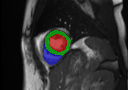

GTnnUNetUNETR+Ours SA/LA onlyOurs AllRefer to captionRefer to captionRefer to captionRefer to captionRefer to captionRefer to captionRefer to captionRefer to captionRefer to captionRefer to captionRefer to captionRefer to captionRefer to captionRefer to captionRefer to caption

Figure 3: Qualitative segmentation results among nnUNet, UNETR+, and the proposed methods. UNETR+ and the proposed approach in the last column (Ours All) use all sparse CMR sequences as network input, while nnUNet and the second last column (Ours SA/LA) are trained solely with either SA or LA views.